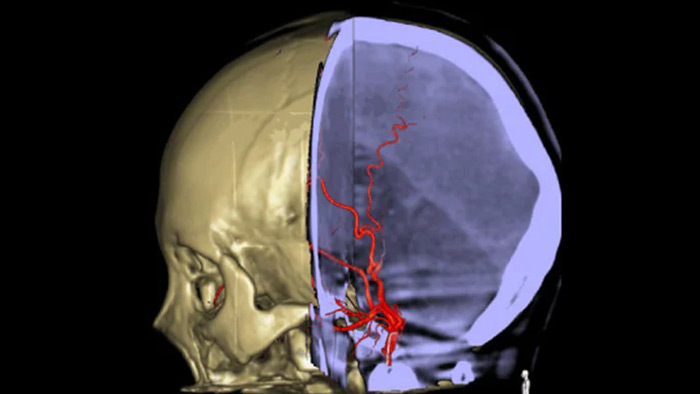

Anatomische Referenzbilder unterstützen die präzise 3D-Navigation

ein Schädel mit roten Adern

SmartCT Roadmap bietet anatomische Referenzbilder zur Unterstützung einer präzisen Navigation von Führungsdrähten, Kathetern und Instrumenten zum Gerinnsel.